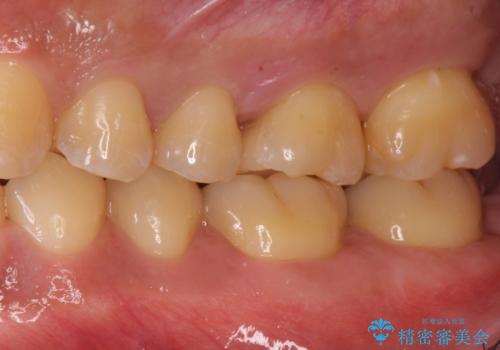

奥歯の虫歯 セラミックインレーに

- 奥歯が虫歯になっていたため、セラミックインレーで修復しています。

治療前の写真では虫歯はわかりにくいですが、レントゲンではっきり見えます。